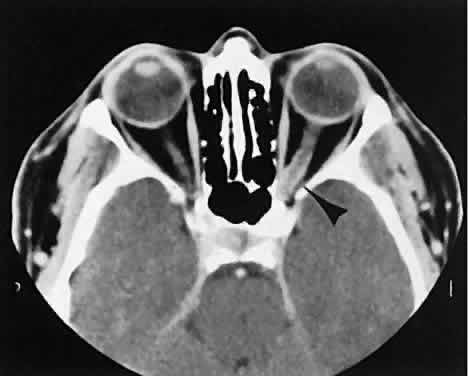

out to represent a varix based on our experience (Fig. 2). Arterial lesions may either have high or low flow. The high-flow lesions are carotid cavernous sinus fistulas and result from a direct communication between the carotid artery and the cavernous sinus. These arise spontaneously or as a result of trauma. The orbit is involved as an innocent bystander, because all signs and symptoms of orbital involvement follow from the retrograde transmission of increased venous pressure from the cavernous sinus. EOMs generally are enlarged, as is the SOV. The ipsilateral cavernous sinus also is enlarged. Intercommunication between the cavernous sinuses also may account for the occasional bilateral findings. Low-flow lesions result from increased blood flow through the cavernous sinus, but the intracavernous carotid artery itself is intact (Fig. 3). These typically are dural-cavernous sinus fistulas. A high index of suspicion may be required to diagnose these, but a fairly stereotyped presentation is a unilateral red-eyed glaucoma with proptosis. Abduction weakness also may be present. Enlargement of one or more EOMs along with an enlarged SOV are noted with CT scanning. A small lesion may escape detection with CT scanning and require high-resolution MRI or even selective internal and external carotid angiography for diagnosis if a high degree of clinical suspicion exists. In a patient with a known dural fistula, a sudden and dramatic deterioration in the clinical picture may be seen with a thrombosis of the SOV.11 The radiographic picture, at least regarding the CT appearance, probably will not change. MRI can nicely show the thrombosis in the SOV.